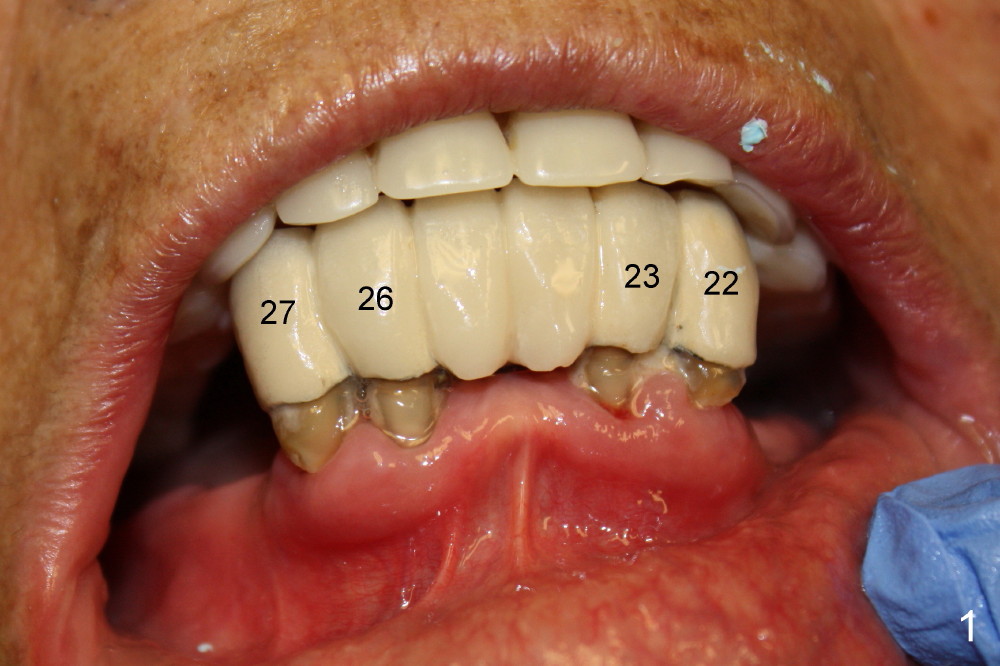

Mrs. Chen, 74 years old, cannot eat properly, because the lower anterior bridge is loose (compare Fig.1 (normal bite) and Fig.2 (edge to edge with lower partial in)). All of these four abutment teeth may have root fracture (Fig.2 >, Fig.4,5). The ridge in the posterior area (Fig.3 black arrows) is much narrower than that of the anterior area (red arrows). The traditional complete denture should have poor retention shortly after anterior tooth extraction with atrophy of the alveolus. Treatment plan is to fabricate the lower immediate complete denture, extract the four remaining teeth (#22,23,26,27), place four immediate implant with ball attachment, and reline the denture with soft reliner initially and retain it with O rings once the implants are osteointegrated.

Since there is limited space between the lower lateral incisor and the canine, implants to be placed should not be too big. For example, if the diameters of the implants at the sites of #22 and 23 are 5 and 4 mm, respectively, there is less than 2 mm of bone between the implants (Fig.5). It is not safe. The bone may die.

It is safer if the diameters are reduced to 4.5 and 3.5 mm, respectively (Fig.4), as recommended by Dr. Borgner as follows. In fact, the implants for the lateral incisors are one piece, whereas those for the canines are two pieces.